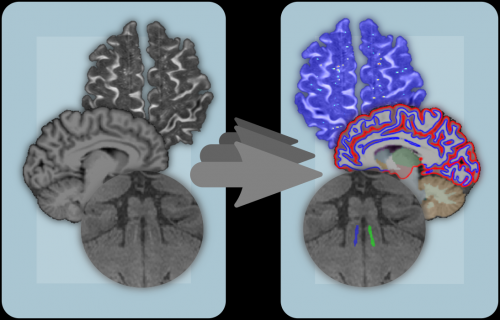

The extraction of features, such as volumes and thickness values, often involves the segmentation of relevant parts of the images, such as certain subcortical brain structures or potentially occurring pathologies like metastases and the effects of microangiopathies. For small patient cohorts, a manual segmentation may be generated with reasonable effort. However, for larger cohorts with hundreds to thousands of individuals, automatic, fast, and robust segmentation algorithms are required.

In this research area, we adapt State-of-the-Art approaches, which usually work well for high quality clinical research data, to data from clinical routine with a reduced quality. Moreover, we develop algorithms in the promising field of deep learning. For instance, in collaboration with the working group “Mixed cerebral pathologies and cognitive aging” (Stefanie Schreiber) at the Department of Neurology at the Otto-von-Guericke University, we address the segmentation of enlarged perivascular spaces in Magnetic Resonance Imaging (MRI) data using neural networks.